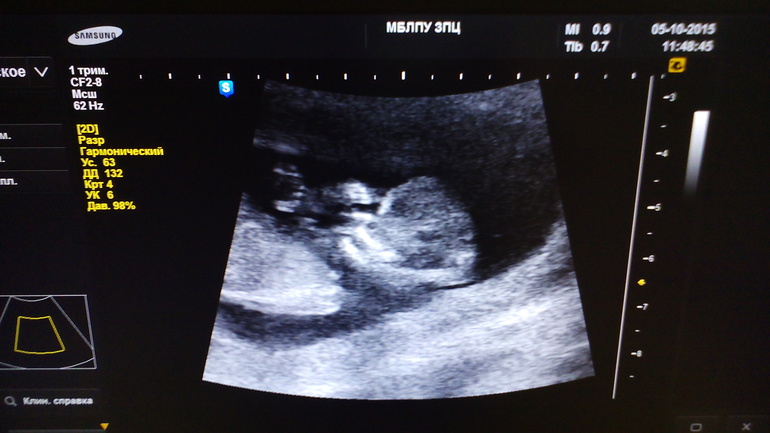

кто читал меня до этого, знает, я устроилась на новую работу, а там напряжонка с нянями, так, что я работаю каждый день с утра! И в понедельник 5 числа я вообще работала в две смены! Утром накормила деток, помыла посуду и бегом на такси в ЗПЦ, а там как всегда очереди длиннющие!!! Пришлось ждать конечно, но оно того стоило)))) я зашла в кабинет, там по сравнению с 2013 годом врачи оказались более приветливые) я легла на кушетку рядом с аппаратом, милая врач начала смотреть нас через животик, хотя с Витой в первый раз там смотрели вагинально. Сначала. Слышала только цифры...цифры да цифры.... А потом включили середечко моей малютки!) аааа!!!! Крошечное середечко моей второй ляли!) и врач сказала, это середчко ребенка)))) потом повернула монитор и показала мою ляличку) и даже разрешила сфотать экран)))) сказала что все хорошо, соответствует срокам и причин для беспокойства нет))))) пока ждала кровь, читала параметры малютки) вот они какие:

Чсс 176 уд мин

Бпр 20,8 мм

Ктр 62,8 мм

Ож 63 мм

Бедро 7,5 мм

Твп 1,3 мм

Носовые кости 2,2 мм

Прикрепление по задней стенке, плацента по краю.

Заключение : беременность 12 нед и 4 дня.

Это на 4 дня больше чем по месячным)))))

А вот и наша крошка)